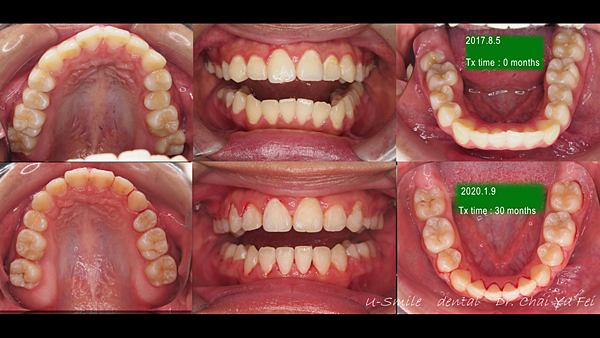

▼ 治療前後の比較 (上顎・下顎)

治療後の写真です。治療前と比較すると、歯が歯列にそってアーチ状にキレイに並んでいるのがわかります。

歯の裏側が見えていた第二大臼歯の傾斜も改善されているのがわかります。

▼ 治療前後の比較 (側方)

どちらの写真も、歯の傾斜が改善されているのがよくわかる写真です。

見た目だけでなく、上の歯と下の歯がしっかりと噛み合うようになり、患者様に喜んでいただけました。

矯正後害羞的她稍稍展開了笑顏~原本暴牙的情形也改善了許多。